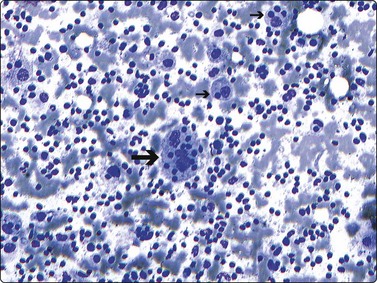

image

Fig. 17.4 Neuroblastoma

Compared with neuroblastic cells, neoplastic ganglion cells (arrows) demonstrate larger nuclei with prominent nucleoli, and moderate amounts of coarsely granular cytoplasm. These cells are seen in the two related lesions, ganglioneuroblastoma and ganglioneuroma (Diff-Quik, ×400).